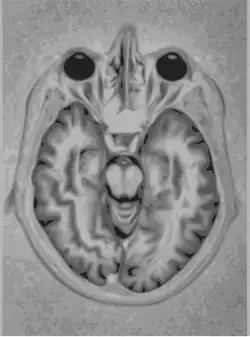

- Ressonância Magnética

Ressonância Magnética (MRI) é uma tecnologia de imagem médica que usa ondas de rádio e um campo magnético para criar imagens detalhadas de órgãos e tecidos. MRI provou ser altamente eficaz no diagnóstico de uma série de condições, mostrando a diferença entre normais e doentes tecidos moles do corpo. A RM é frequentemente utilizada para avaliar:

- Veias de sangue

- Tecido anormal

- Peito

- Ossos e articulações

- Órgãos na pelve, tórax e abdômen (coração, fígado, rim, baço)

- Lesões na coluna

- Rasgos do tendão e do ligamento.[7]

A Ressonância Magnética Nuclear (RMN) utiliza ímãs potentes para polarizar e excitar os núcleos de hidrogênio (prótons individuais), que são amplamente encontrados no tecido humano. O scanner usa antenas para produzir pulsos de ondas de rádio na frequência de ressonância dos átomos de hidrogênio nas moléculas de água. As ondas de rádio geradas em resposta são codificadas e resultam em imagens do órgão desejado.[9]

Nas técnicas com raio-X, apenas os tecidos densos criam boas imagem, sendo muito difícil avaliar tecidos pouco densos como o tubo digestivo e o sistema reprodutor. Assim, pode ser usado para investigar tumores, o fluxo de sangue do coração, função renal e função pulmonar.